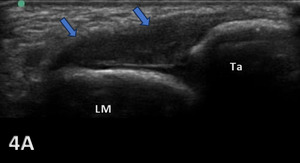

COMPLETE TEAR OF ATFL

Figures 4A: LAX ultrasonography of the ATFL shows hypoechoic discontinuity of the ligament, compatible with a complete tear (blue arrows). An inversion stress image provides more diagnostic confidence regarding the complete tear. LM, lateral malleolus; Ta, talus